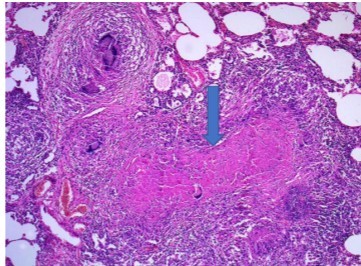

What kind of granuloma is this?

Caseous